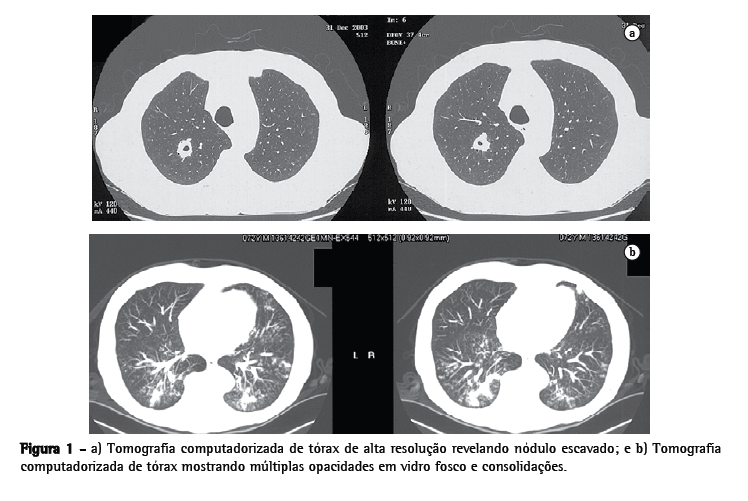

Um homem de 71 anos de idade, recentemente diagnosticado com síndrome de Cushing devido a um tumor adrenal, queixava-se de tosse, dispnéia e febre. Ao exame físico, a saturação periférica de oxigênio em ar ambiente era de 88%. Os exames laboratoriais revelaram anemia, plaquetopenia e níveis elevados de aminotransferase hepática, além de colestase, hipertrigliceridemia e um nível extremamente alto de ferritina sérica (10.580 μg/L; faixa normal, 20-250 μg/L). A colangiopancreatografia por ressonância magnética e ultra-sonografia normais excluíram a hipótese de obstrução do sistema biliar. A fim de investigar a anemia, foi realizada aspiração da medula óssea, cujos resultados foram compatíveis com o diagnóstico de SAM. Os resultados da cultura de aspiração foram negativos. Uma TC do tórax revelou um nódulo escavado, juntamente com opacidades em vidro fosco e consolidações (Figura 1). Realizou-se, então, uma broncoscopia. As culturas do lavado broncoalveolar foram negativas, e uma biopsia transbrônquica do lobo inferior direito mostrou abundantes macrófagos com hemossiderina nos espaços alveolares, bem como ausência de pleomorfismo significativo ou atividade mitótica. Havia infiltração linfocítica nos septos alveolares, que apresentavam espessamento. Estes achados histológicos também são compatíveis com SAM. Considerando-se este diagnóstico, iniciou-se pulsoterapia com imunoglobulina humana intravenosa (1 g/kg diariamente por 2 dias).(1) Após 20 dias, desapareceram a anemia, as alterações hepáticas, os infiltrados pulmonares e a hipoxemia, e o nível de ferritina sérica normalizou-se. Três anos após o tratamento com imunoglobulina, os achados da TC do tórax e os resultados dos exames laboratoriais estavam normais e o paciente não apresentava queixas.

Este foi o primeiro relato de caso no qual foi observada a combinação de nódulo escavado, opacidades em vidro fosco e consolidações pulmonares numa TCAR (Figura 1). Este achado é importante porque inclui a SAM no diagnóstico tomográfico diferencial de pneumonia, linfoma, vasculite pulmonar, hemorragia alveolar, tuberculose, pneumocistose, nocardiose e doença fúngica.(5-9)